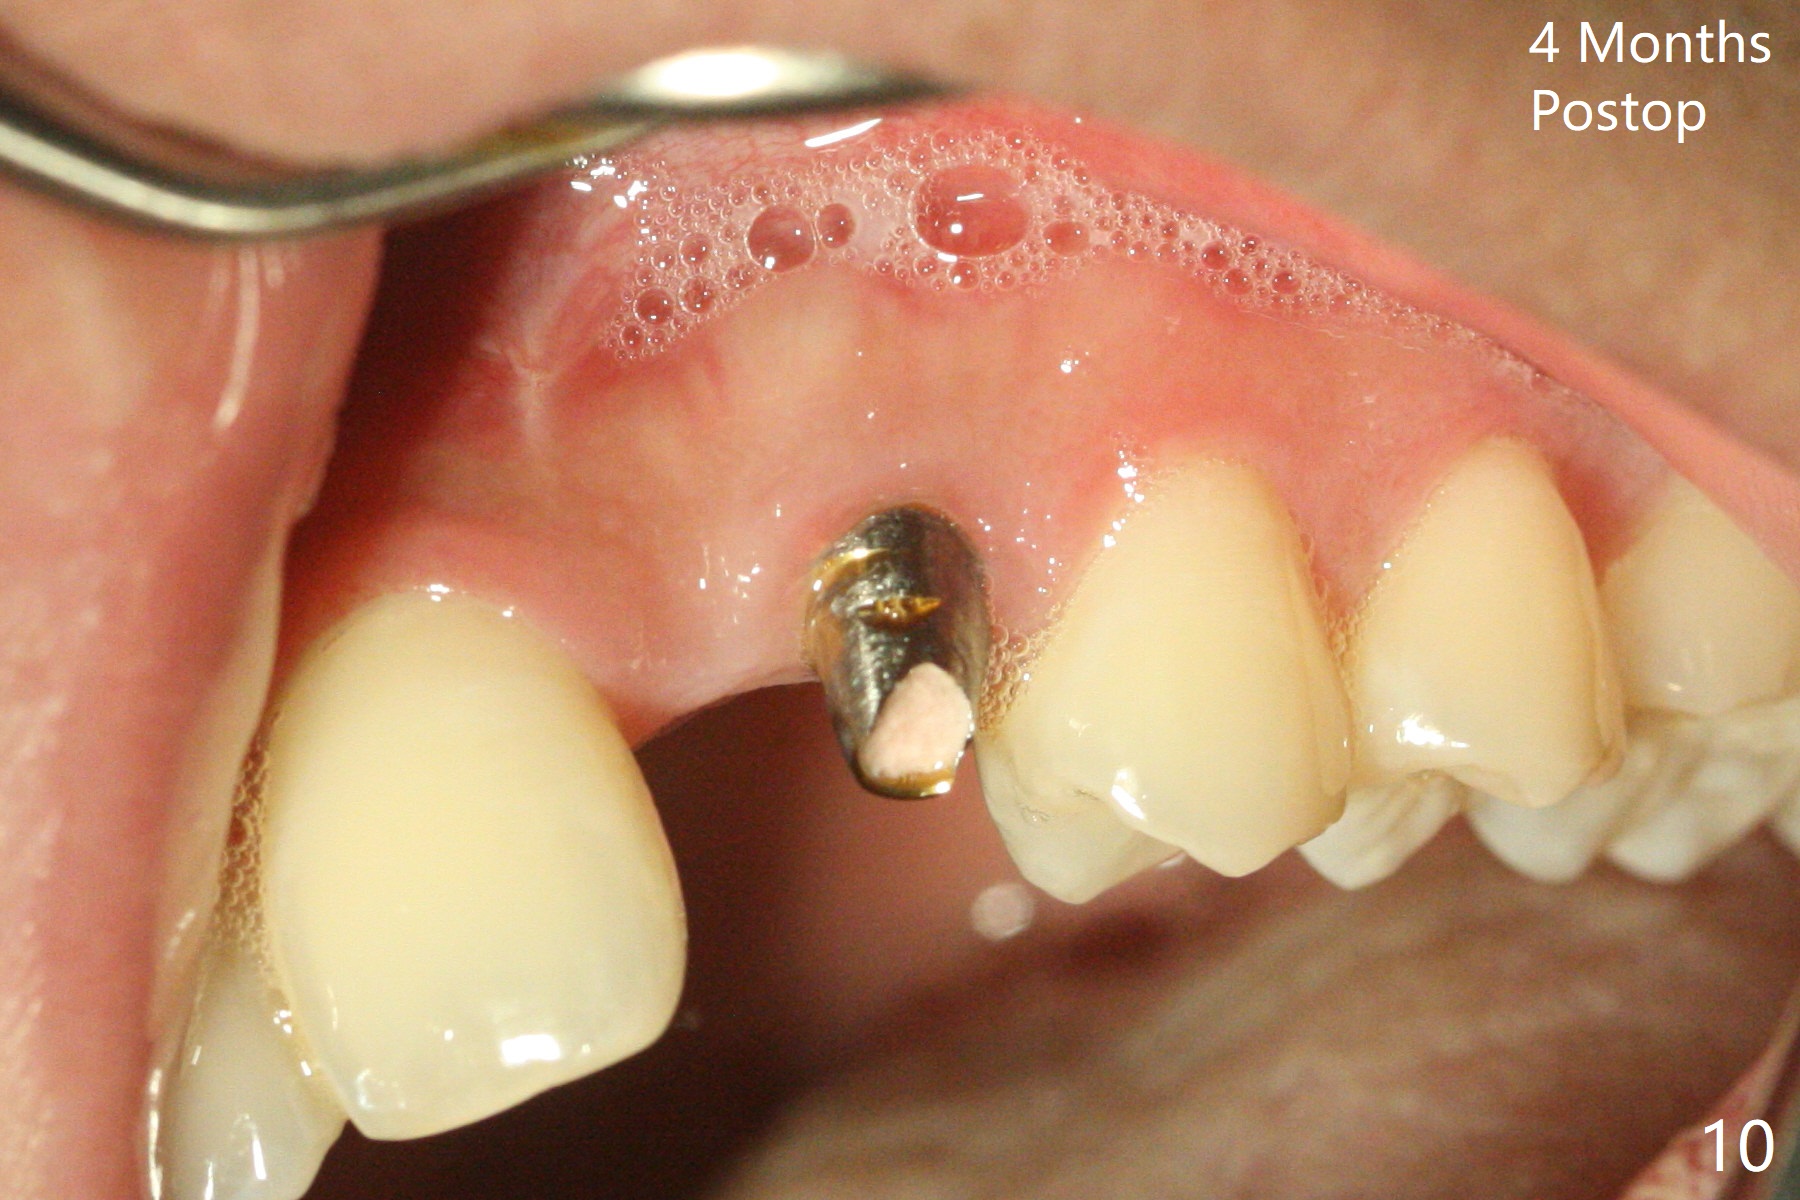

18岁男,本月底到外州上大学,急于十九岁前完成治疗,保险可以多付些。术前检查显示双侧尖牙(图一,二 6,11)根尖,侧切牙牙槽嵴萎缩(*),尖牙、侧切牙之间颊侧做垂直切口,骨膜下潜行分离,在尖牙根尖隧道植骨,然后使用导板,植入窄植体(图四至六),接近或者穿过上颌窦底板(图三,四箭头),骨粉(粘性骨块做的不成功,图五,六 *)好像覆盖暴露的螺纹。再次补充隧道骨粉后,放置修复基台(图七,八),调整后(图九),取模做临时悬臂桥,临床上有些困难分配尖牙,侧切牙比例。术后4个月左侧植体愈合正常(图十,十一),而右侧感染。